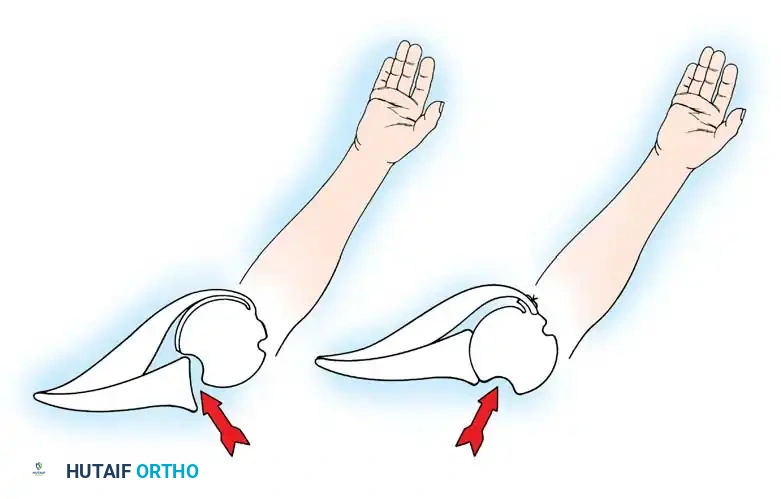

The musculature surrounding the shoulder provides essential dynamic stability. The deltoid produces primarily vertical shear forces, tending to displace the humeral head superiorly. To counteract this, the intrinsic muscles of the rotator cuff provide compressive forces. Lippitt and Matsen described "concavity compression," wherein the dynamic contraction of the rotator cuff compresses the humeral head into the concave glenoid socket. Loss of the labrum reduces this stabilizing effect by up to 20%.

Glousman et al. highlighted that synchronous eccentric deceleration and concentric contraction of the rotator cuff and biceps are vital for stability during mid-ranges of motion. Asynchronous fatigue from overuse or incompetent ligaments leads to microtrauma. MRI studies frequently reveal fatty infiltration and thinning of the subscapularis tendon in chronic recurrent anterior instability.

Furthermore, scapulothoracic kinematics play a massive role. Rowe, Kummel, and later Lippitt and Matsen emphasized that synchronous mobility of the scapula ensures the glenoid is optimally positioned beneath the humeral head, converting potential shear forces into compressive forces. Jobe and Glousman advocated for rigorous strengthening of scapular stabilizers (serratus anterior, trapezius, rhomboids) in overhead athletes. Proprioceptive feedback, mediated by Ruffini end organs and Pacinian corpuscles within the capsule (as demonstrated by Vangsness et al.), is also critical for dynamic neuromuscular control.